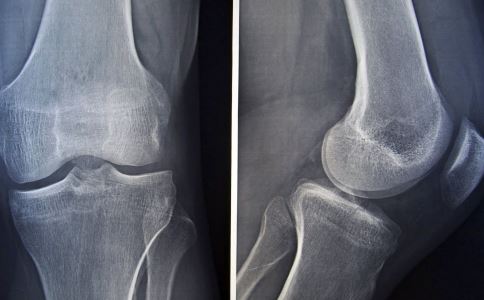

腰背疼痛是腰椎间盘突出吗?

腰背疼痛是人们日常生活中经常遇到的一种病症,这其中很大一部分是由于腰椎间盘突出引起的。这种疾病常见于20-50岁的病人,男女比例约为4:6。

病人多从事需要经常弯腰劳动或者是长期端坐的工作,例如如:司机、公司白领,搬运工,建筑工人等都是腰椎间盘突出症的高危人群,同时吸烟、不经常锻炼、过度肥胖也会增加患该病的风险。专家提示,此类人群如果经常出现腰背疼痛的症状,一定要及早检查,警惕腰椎间盘突出的发生。

腰椎间盘突出的症状

腰背疼痛是腰椎间盘突出最主要的病症表现,并且有时候会伴随有腿疼的出现。

95%以上的腰椎间盘突(脱)出症患者有此症状,包括椎体型者在内。

由于椎间盘突出95%都发生在腰4、5和腰5骶1之间,故多伴随有坐骨神经痛。疼痛为放射性,由臀部、大腿后外侧、小腿外侧至跟足部或者足背。疼痛可在喷嚏或者咳嗽时由于负压增加而加重。

有少数病例(约5%~10%)自觉肢体发冷、发凉,主要是由于椎管内的交感神经纤维受刺激之故。临床上常可发现手术后当天患者主诉肢体发热的病例,与此为同一机制。

中央型的腰椎间盘突出如果压迫到马尾神经,可能会出现大小便障碍,鞍区感觉异常。